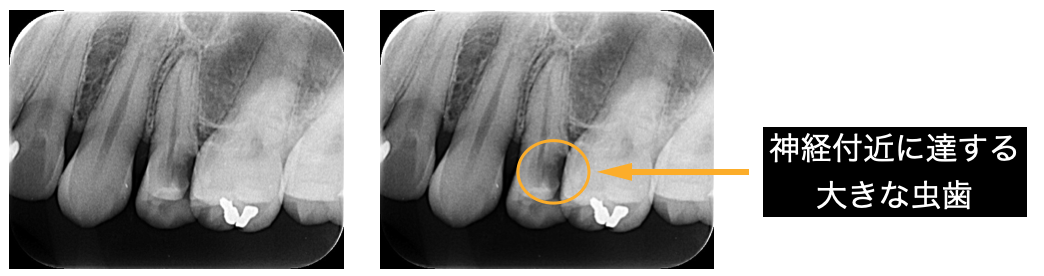

①虫歯が以前より深くに達した。

虫歯の存在に気づかなかったり、症状がないため放置していると虫歯は深くまで進行してしまいます。

神経付近にまで虫歯が達すると、冷たいものを飲んだ後長時間しみたり、温かいものがしみてくることもあります。

そこまでいくと神経の処置が必要になることもあります。